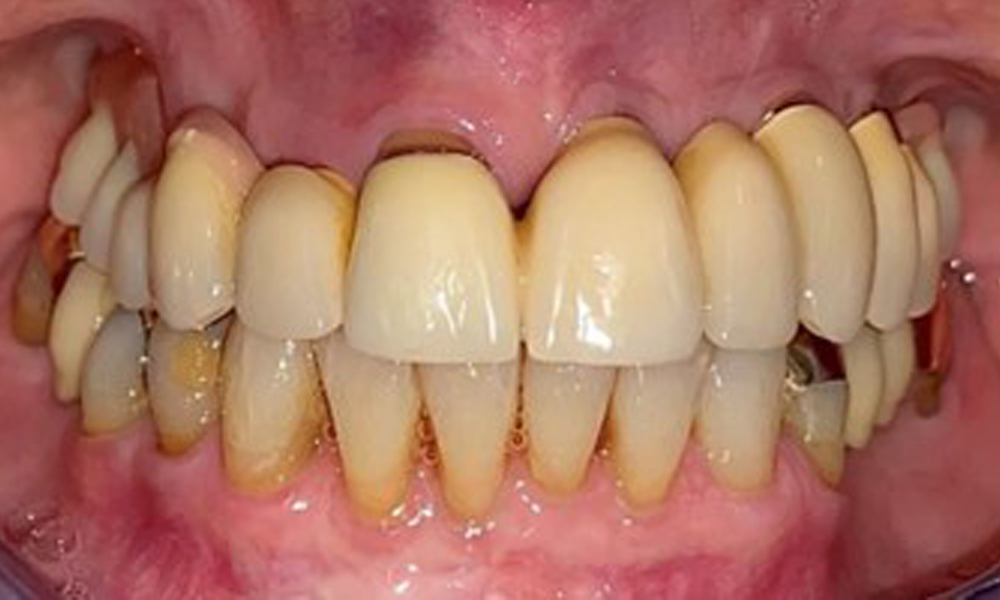

The patient was fitted with a combined removable maxillary telescopic prosthesis more than 25 years ago (Fig. 1, Fig. 2, Fig. 3) and is very happy with her dentures. The patient has an adequate fixed denture for the mandible (Fig. 4).

The dental findings are as follows: Combined removable implant and tooth-supported telescopic prostheses on implants 15, 13, 21, 23, 24, 25 and tooth 11 (Fig. 1, Fig. 2, Fig. 3). The patient was fitted with a fixed mandibular denture. Adequate bridges were present over 37 to 34 and 45 to 47 (Fig. 4), the crown margins were intact and there were no active caries. A composite filling with a marginal gap was present on tooth 43. There was mandibular gingival recession, exposing 1 to 3 mm of root surface. This also applies to 11.

The periodontal condition remains stable. There was no gingival or peri-implant soft tissue inflammation. At 1 to 3 mm, the probing depths were within the physiological range. There are generalised recessions measuring 1 to 3 mm. Implant 23 has an increased probing depth of 4 mm, although there are no signs of secretion or bleeding (Fig. 6). The total BOP is 12%.